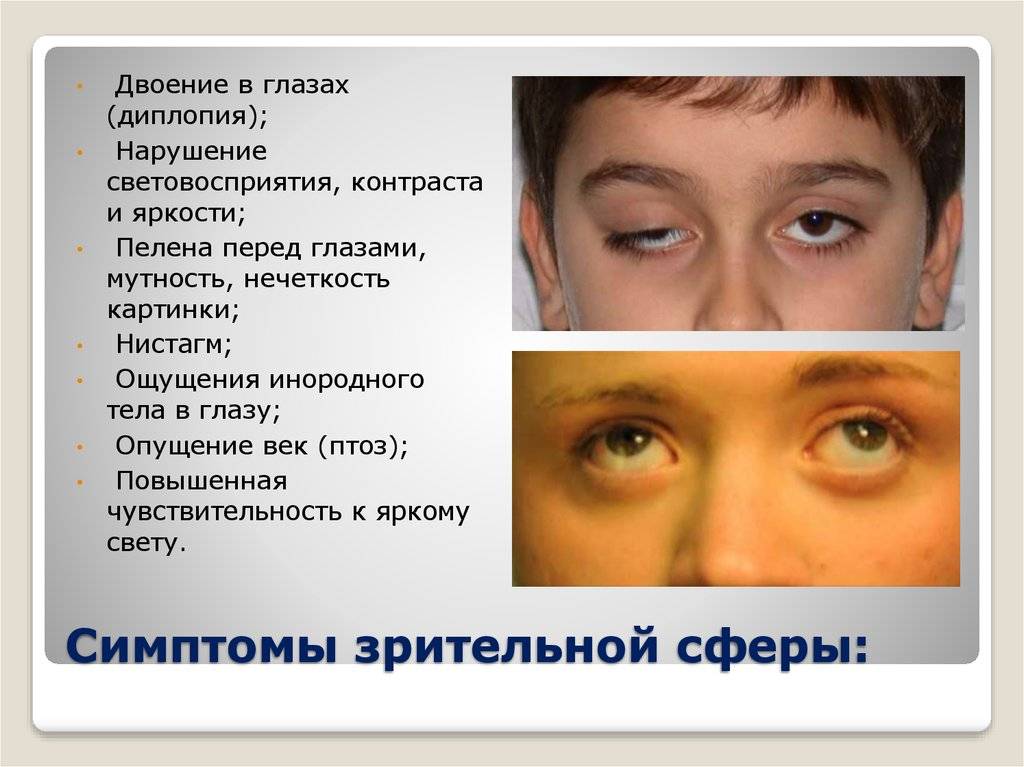

Диплопия: механизм развития и методы лечения